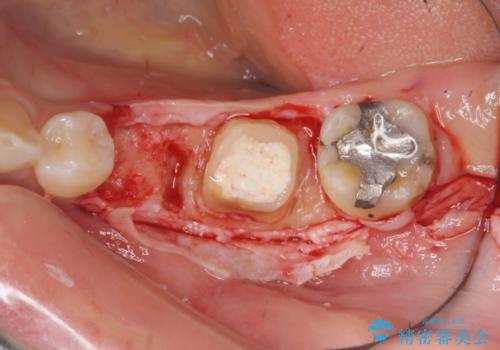

ブリッジ治療の予知性を高めるために、虫歯の徹底的な除去に加え縁上歯質を確保するための歯周外科手術、マイクロスコープを用いた精密根管治療を行う治療計画としました。

外科処置の注意事項(リスク・副作用など)

- 外科手術のため、術後に出血、痛みや腫れ、違和感を伴います

- 口腔内の状態によっては適応できないことがあります